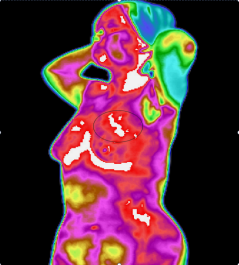

近期,广东省第二人民医院(以下简称“省二医”)疼痛科引入了红外热像检查系统,能够快速准确探测到目标物的温度变化情况,并将其转化为温度值图像,再通过专业的图像分析工具,帮患者把疼痛感受客观“描述”出来,在不接触、无辐射的情况下使疼痛形象化,大大提高诊断的准确率和治疗的有效率!

4.高敏感度:能极其敏感地接收人体细胞新陈代谢所产生的热辐射(小于0.025 ℃ ),显示人体内异常热源的分布、深度、强度、形态及走势;